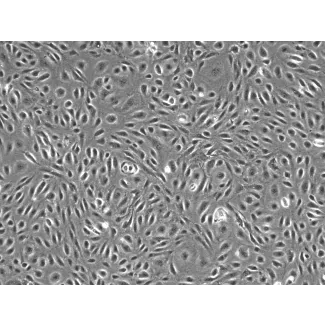

Cells of the dura mater, such as mast cells, macrophages, fibroblasts, and microvascular endothelial cells contribute in varying degrees to headache pathophysiology, but also provide critical normal functions. Dural fibroblasts (DuF), for instance, in the healthy brain produce extracellular matrix proteins such as collagen and fibronectin. Dural endothelial cells regulate blood vessel function in the meninges and serve as a selective barrier for the diffusion of cells and macromolecules into and out of the bloodstream. In addition, dural endothelial cells play an important role in vascular signaling, tone, remodeling, and inflammation. In recent studies, both dural fibroblasts and dural microvascular endothelial cells have been linked to migraine pathophysiology by activating and sensitizing meningeal afferents through the release of pro-inflammatory factors. To aid researchers in studying migraines and headaches, we are now offering normal human primary Dural Fibroblasts and Dural Microvascular Endothelial Cells. Human Dural Fibroblasts (Cat. #1420) and Human Dural Microvascular Endothelial Cells (Cat. #1430) are useful in vitro models to further elucidate the role of dural cells in migraine pathophysiology.